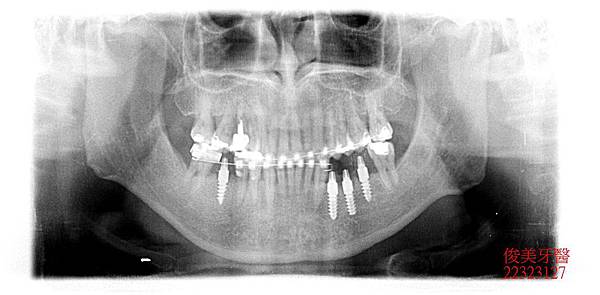

缺牙區皆在後牙咀嚼重力區,因此皆以植牙做修復,以支持整個咬合力量,減輕前牙的受力。

外觀暴牙幅度已縮小改善,臉型較為放鬆,肌肉不緊蹦。

治療結束,半年後追蹤,狀況維持的不錯,患者相當滿意,目前仍配戴維持器。定期檢查即可。 ※牙科門診時間:星期一至星期六 預約患者優先看診。 預約專線:04-22323127 |